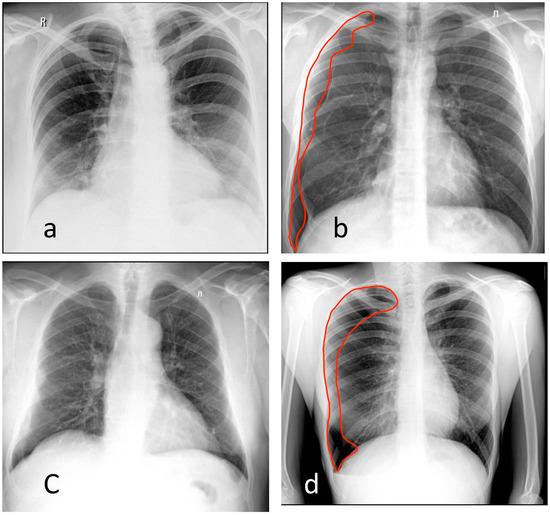

3.1. Chest X-ray

3.2. Chest Digital Fluorography (FLG)